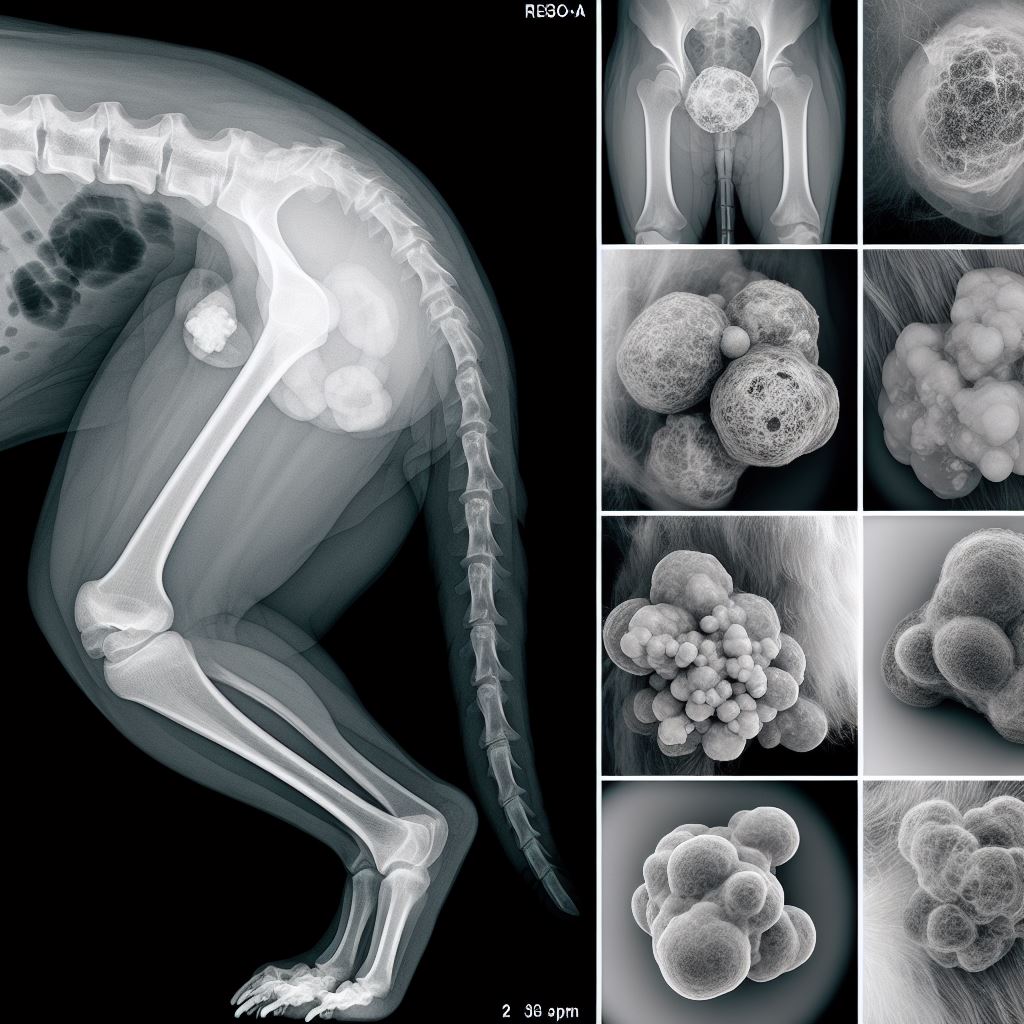

강아지 지방종1강아지 지방종2강아지 지방종3

강아지 지방종 사진

강아지 지방종4강아지 지방종5강아지 지방종6

강아지 지방종7강아지 지방종8강아지 지방종9

강아지 지방종10강아지 지방종11강아지 지방종12